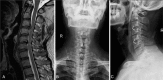

Comparing the clinical and radiographic outcomes in anterior cervical discectomy and fusion (ACDF) using a zero-profile anchored spacer (ROI-C) or a conventional cage-plate construct (CPC) for treating noncontiguous bilevel of cervical degenerative disc disease (CDDD).Overall, 46 patients with 2 noncontiguous segments of CDDD, treated with ACDF from January 2011 to October 2015, were included in this study. ROI-C was used in 22 patients (group A) and CPC in 24 patients (group B). The clinical and radiographic outcomes and complications were compared pre- and postoperatively. All patients were followed up for at least 24 months after surgery.No significant difference was found in fusion rate, cervical curvature, height of fused segment (FSDH), intraoperative blood loss, and Japanese Orthopaedic Association (JOA), and Neck Disability Index (NDI) scores between the 2 groups. Group A had a shorter operation time and significantly lower incidence of dysphagia (3 and 24 months postoperatively) than group B (P < .001 and P < .05, respectively). Moreover, group A had a higher loss of FSDH than group B, but with no difference between the 2 groups (P > .05). Two cages developed subsidence in group A (4.5%) and 2 adjacent levels developed degeneration in group B (2,8%).ACDF with ROI-C device was superior to CPC for noncontiguous bilevel of CDDD because it avoided postoperative dysphagia and required a shorter operation time. Moreover, the clinical outcomes were comparable. Prospective trials with larger samples and longer follow-up are required to confirm the results.